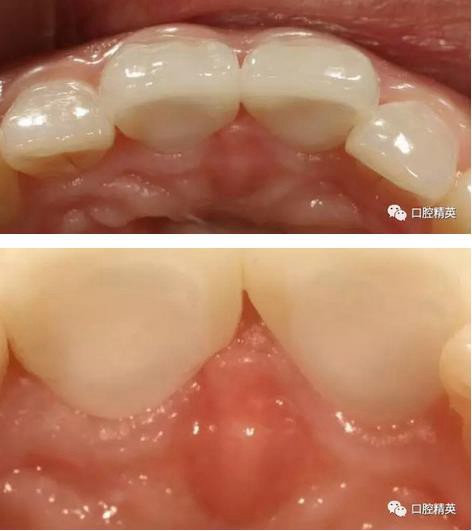

口內(nèi)正側(cè)位及切端特寫

術(shù)前,術(shù)中,術(shù)后對(duì)比

對(duì)比來看基本達(dá)到患者預(yù)期

有一點(diǎn)不足之處在于齦緣的高低不完全一致,補(bǔ)救辦法同上——激光輕掃